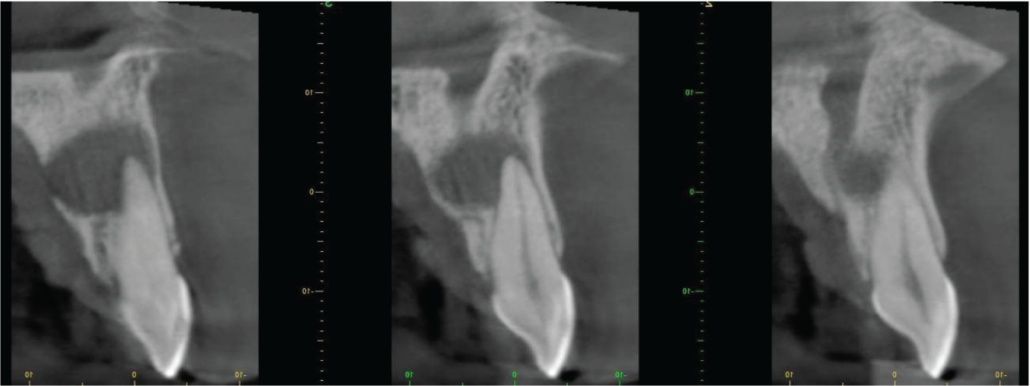

The lesion extends mesially to involve the UL1 root apex and reaches the nasopalatine canal. The upper margin of the lesion is clear of the nasal floor (image 3).

Labio-palatal cross-sections of UL1